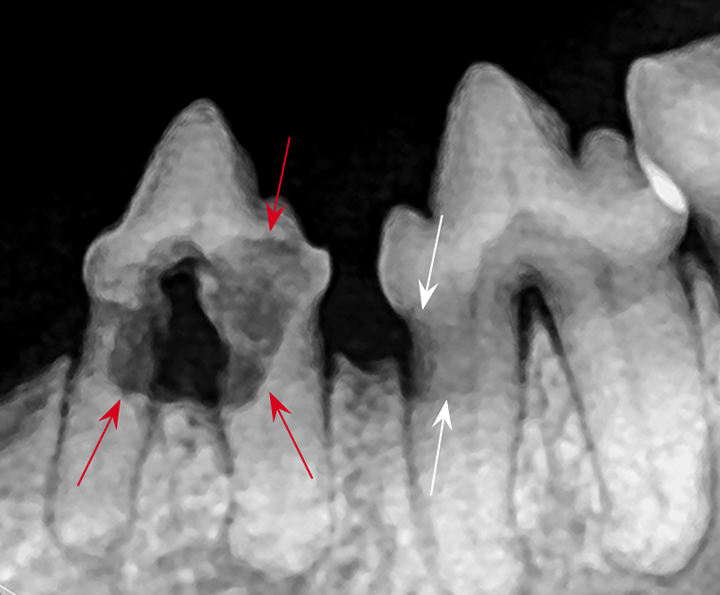

From pocketdentistry.com

Radiographic Appearance of Dental Tissues and Materials Pocket Dentistry Dental Radiographs Are Not Used For Cavities, infections, and other conditions show up as dark spots on the lighter image of the tooth. Click the card to flip ๐. Which is not a use for panoramic radiographs in dentistry? Diagnosis of decay, periodontal disease, or periapical. Dental radiographs are a useful and necessary tool in the diagnosis and treatment of oral diseases such as caries, periodontal. Dental Radiographs Are Not Used For.